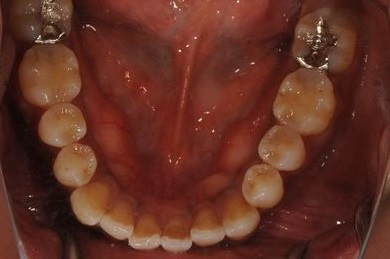

| 治療内容 | インプラント2本(ソケットリフト、抜歯即日スピードインプラント)、メタルボンドセラミッククラウン3本(メタルボンドセラミック用土台1本)、ハイブリッドセラミックインレー4本 | ||||||||||||||||||||||||||||||||

| 治療期間 | 10ヶ月 |

治療前